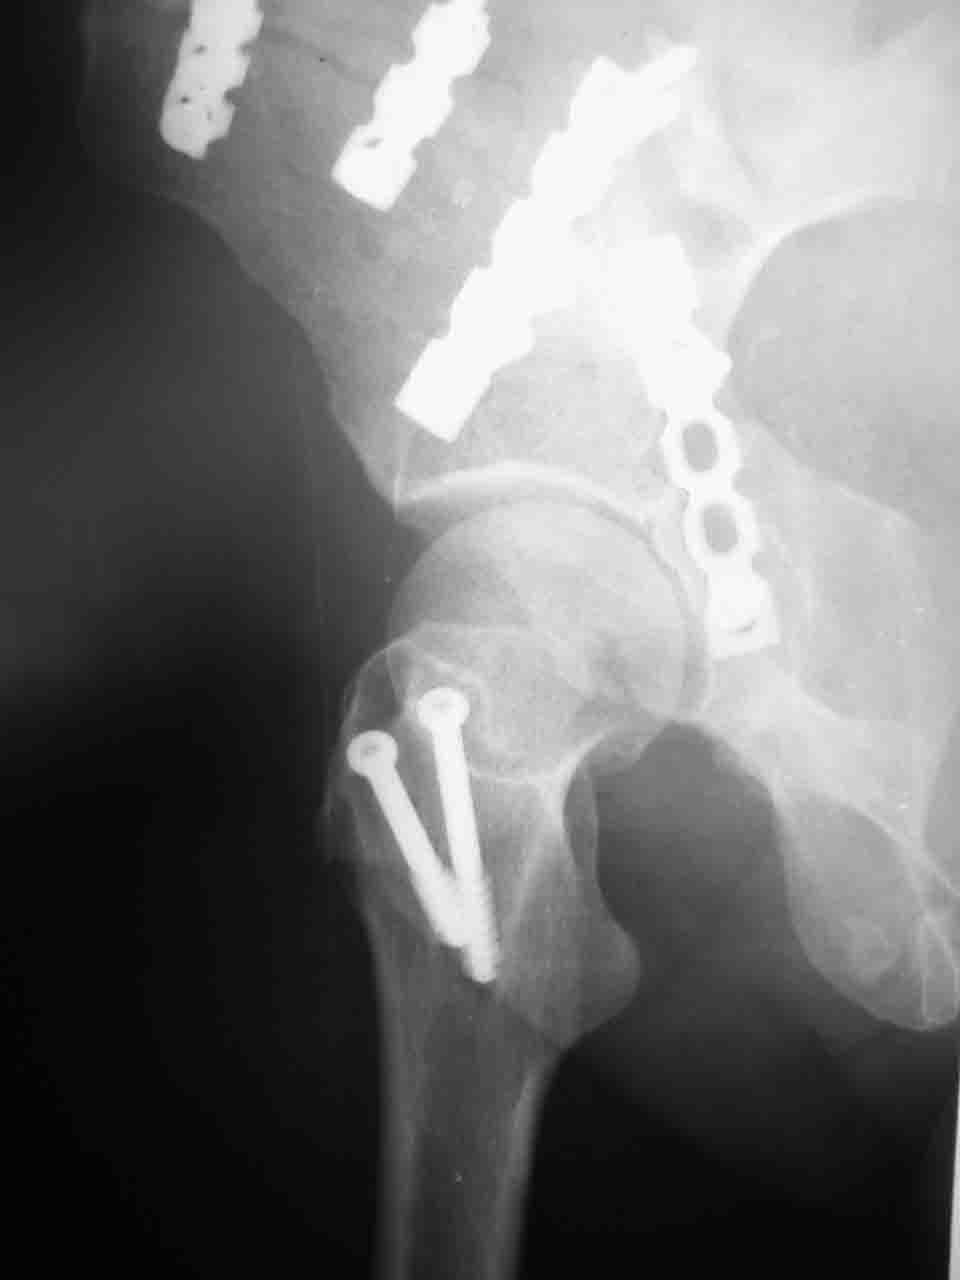

А какой отдел вертлужной впадины более важен передний или задний? Чем был обусловлен выбор доступа к суставу? Проще говоря, почему вы пошли передним доступом на двухколонный перелом? Мне понятны ваши сомнения, когда не удется сделать все что хотелось бы. В данном случае доступ должен быть чрезвертельным боковым (как и советовал Рунков) или двумя доступами.

Интерес к реконструкции вертлужной впадины у меня появился довольно-таки давно, но до недавнего времени как-то не ощущалась готовность к практической реализации, а местный подход достаточно консервативен - перелом срастется,

а далее будет видно. Такую точку зрения я не разделяю, поэтому через конференции,ортофорум и свои случаи пытаюсь практически и теоретически *продвинуть* для себя тему реконструкции вертлужной впадины.

Логика подсказывает, что все-таки лучше иметь анатомически полноценную впадину, хотя ранее упоминалось состояние вторичной конгруэнтности и одно наблюдение у меня есть, когда у больного с полностью нарушенной анатомией впадины и подвывихом головки бедра кзади и кверху боли отсутствовали при относительно достаточном для стиля жизни больного объёме движений. Но это только одно наблюдение и кроме перелома впадины у этогобольного была и тяжелая ЧМТ в анамнезе. Основываясь на формулировке структуры ацетабулюм Э. Летурнеля - как перевернутой буквы Y, впадина для полноценной функции сустава должна иметь сферичность, соответствующую размеру головки бедра и если один из компонентов в дефиците, то функциональные последствия рано или поздно проявятся.

Сложностью, ассоциативностью характера перелома, я бы с радостью воспользовался мининвазивной перкутанной фиксацией винтами, но боюсь, что результат был бы ещё хуже, техникой непрямой репозиции перелома не владею, поэтому пытаясь получить анатомичную впадину приходится широко открывать, по крайней мере пока, а дальше буду пытаться уменьшать пространство...

> передним доступом на двухколонный перелом?

Илеофеморальный доступ не совсем передний и сравнительно с илеоингвинальным, и Кохера-Лангенбека открывает весь наружный таз кроме самых передних отделов лонных костей, фиксацию которых я не ставил в задачу. Обширность диссекции, большая длительность операции и более высокий риск гетерооссификации - отрицательные моменты в обмен на возможность легче ориентироваться.

Вопрос доступа к вертлужной впадине при остеосинтезе задача не простая. Конечно, у Летурнеля и Тайла всё давно описано, нам остается только брать на вооружение. Но сами понимаете, что не бывает двух одинаковых ситуаций, поэтому в каждом случае вопрос решается сугубо индивидуально. Наша главная цель - восстановить анатомию с нанесением минимальной дополнительной травмы тазобедреннному суставу, думаю с этим никто не поспорит. Расширенный илиофеморальный доступ уж слишком травматичен (как сказал один коллега "таз лежит отдельно, больной отдельно").Стоит ли делать из пациента анатомический препарат для того чтобы легче ориентироваться. Да и нужно ли собирать всю "мозаику"? Мы применяли при таких операциях своеобразную операционную хитрость - сначала устраняли грубое смещение крыла под гребнем с фиксацией так называемой "плавающей" пластиной (временно фиксированной на двух винтах)- доступ или продлевали боковой, или делали небольшой дополнительный разрез над гребнем. Это позволяло устранить грубое смещение и захождение отломков тела повздошной кости, что значительно облегчало репозицию и остеосинтез впадины над сводом. Основное внимание конечно же уделяли нагружаемому задне-верхнему отделу. Сообщите ваш адрес, пришлю схемы и рентгенограммы.